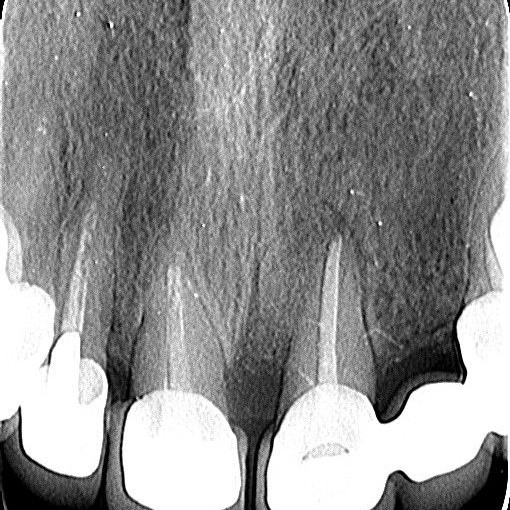

Regenerativni parodontološki zahvat kojim se kirurškim putem regenerirao infrakoštani defekt(parodontološki džep)